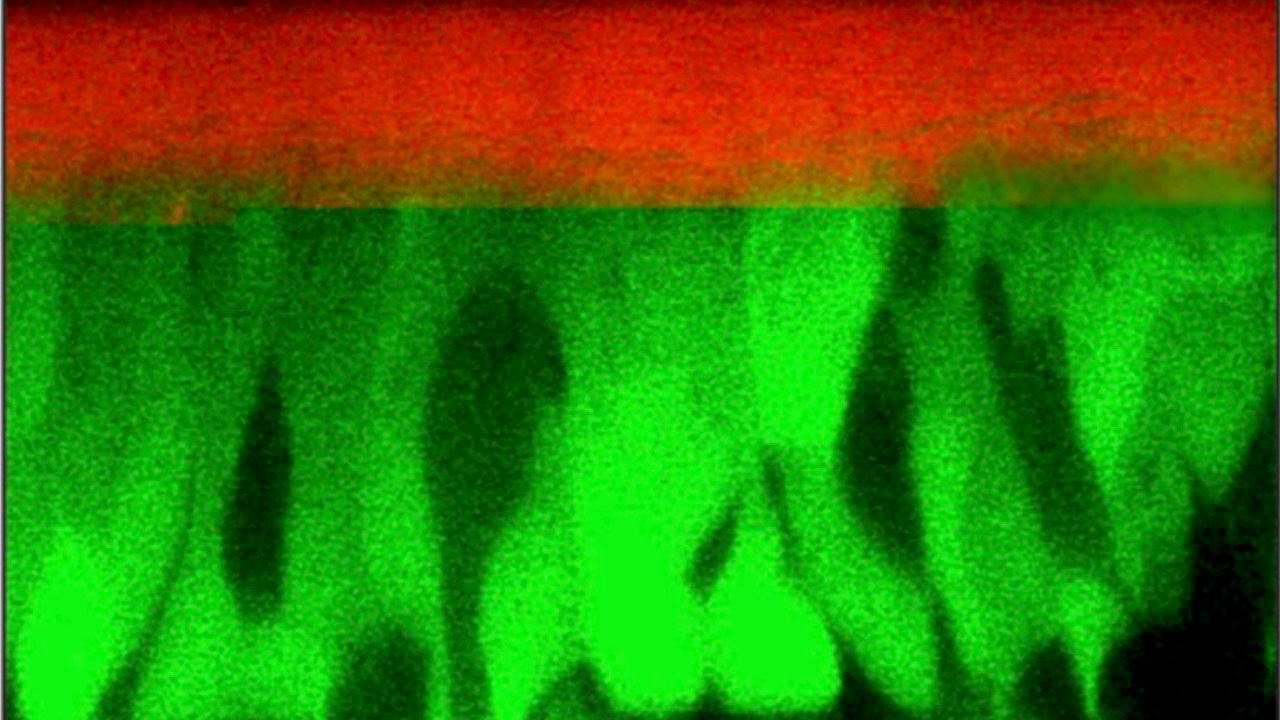

Exposing airway liquid interface cultures of human bronchial cells to dry air  thins mucus, compressing cilia and airway epithelial cells, and secreting inflammatory cytokines.